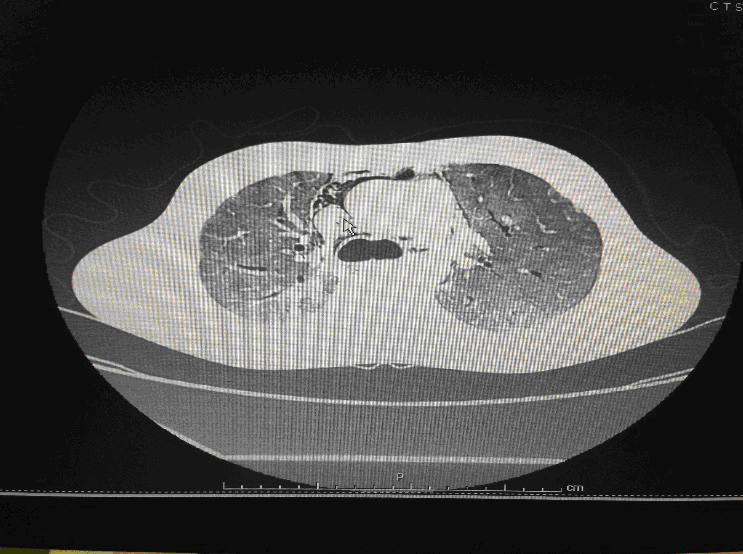

Following admission in the Medical ICU, Bronchoscopy was done and started on IV steroids and higher End Antibiotics. His bronchial wash grew ESBL Klebsiella and Pseudomonas. His other organ functions were not deranged. Repeat CT Thorax was taken which showed ground glass opacities, septal thickening, traction bronchiectasis, pleural thickening which was all S/o Drug induced Toxicity-Bleomycin.

High-resolution computed tomography (HRCT) of the chest is more sensitive than chest radiography in identifying lung abnormalities in bleomycin-exposed patients. HRCT patterns usually reflect the underlying histopathology . Diffuse alveolar damage is associated with airspace consolidation and ground-glass opacities. Findings suggestive of end-stage fibrosis include extensive reticular markings, traction bronchiectasis, and honeycombing. Organizing pneumonia manifests as ground-glass opacities in a bilateral but asymmetric pattern or by airspace consolidation with a subpleural or peribronchial distribution. Organizing pneumonia may occasionally present as one or more nodular densities that may mimic tumor metastases.